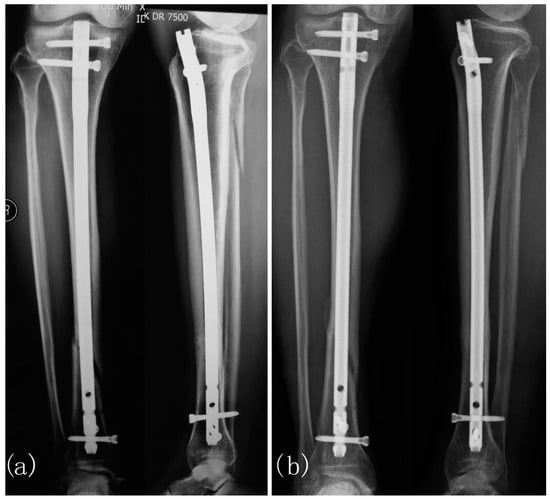

- Cebrián, J.L.; Gallego, P.; Francés, A.; Sánchez, P.; Manrique, E.; Marco, F.; López-Durán, L. Comparative study of the use of electromagnetic fields in patients with pseudoarthrosis of tibia treated by intramedullary nailing. Int. Orthop. 2010, 34, 437–440. [Google Scholar] [CrossRef] [PubMed]

- Del Buono, A.; Zampogna, B.; Osti, L.; Fontanarosa, A.; Garofalo, R.; Papalia, R. Pulsed Electromagnetic Fields after Intramedullary Nailing of Tibial Fractures: A Case Control Study. Int. Orthop. (SICOT) 2021, 45, 2945–2950. [Google Scholar] [CrossRef]